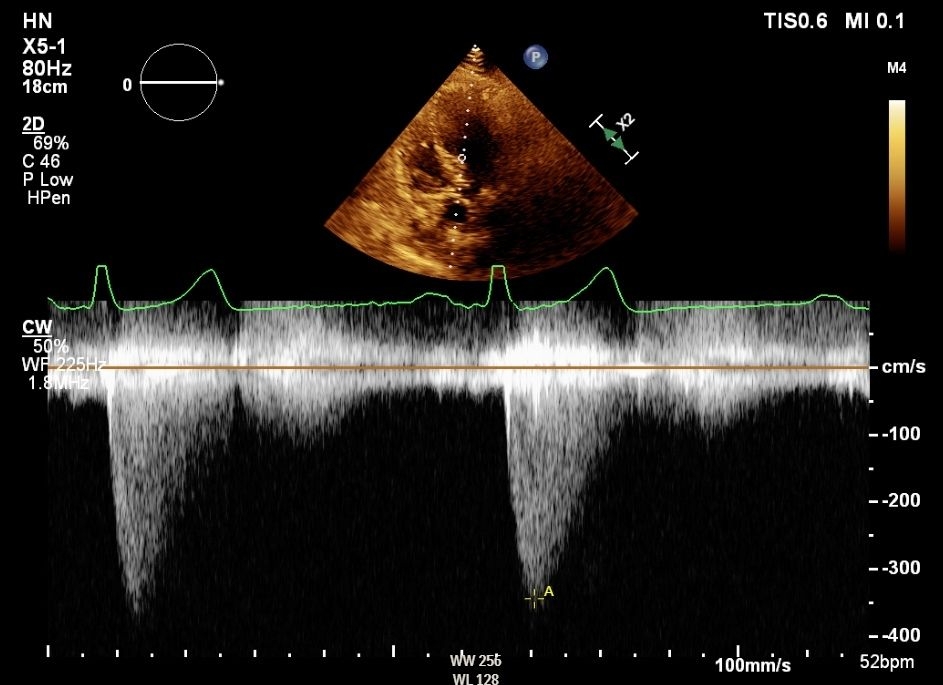

A 68-year-old male with history of hypertension was referred from another hospital for aortic valve (AV) replacement evaluation due to a few months of progressively worsening exertional chest pain and dyspnea. Exam was notable for a crescendo decrescendo systolic murmur; the patient was otherwise hemodynamically stable. ECG on arrival revealed left axis deviation and voltage criteria for left ventricular hypertrophy. Transthoracic echocardiography (TTE) report from the outside hospital mentioned “moderate to severe AS”. On admission repeat TTE revealed chordal systolic anterior motion with flow acceleration and significant LVOT pressure gradient up to 60-65mmHg while AV was hard to visualize but did not appear severely stenosed. Significant gradients were noted on continuous wave (CW) doppler of AV (Figure 1) while stepwise pulsed wave (PW) doppler was unrevealing. Based on obstructive physiology noted on TTE, therapy with a beta blocker was initiated. To further evaluate an invasive hemodynamic study was performed which did not reveal a resting gradient (Figure 2) however provocation with isoproterenol revealed LV-Ao (left ventricle to aorta) gradient which was higher with increasing doses (Figure 3). Furthermore, aortic waveform morphology and post PVC (premature ventricular contraction) response also revealed dynamic LVOT obstruction. Transducers were switched to verify findings and catheter pullback did not demonstrate any zero error. A final diagnosis of dynamic LVOT obstruction with no hemodynamically significant AV stenosis was made and patient was discharged on beta blockers with plan to consider septal reduction strategies if symptoms persist despite optimal medical therapy. He stayed asymptomatic and follow up echo did not reveal any gradient.